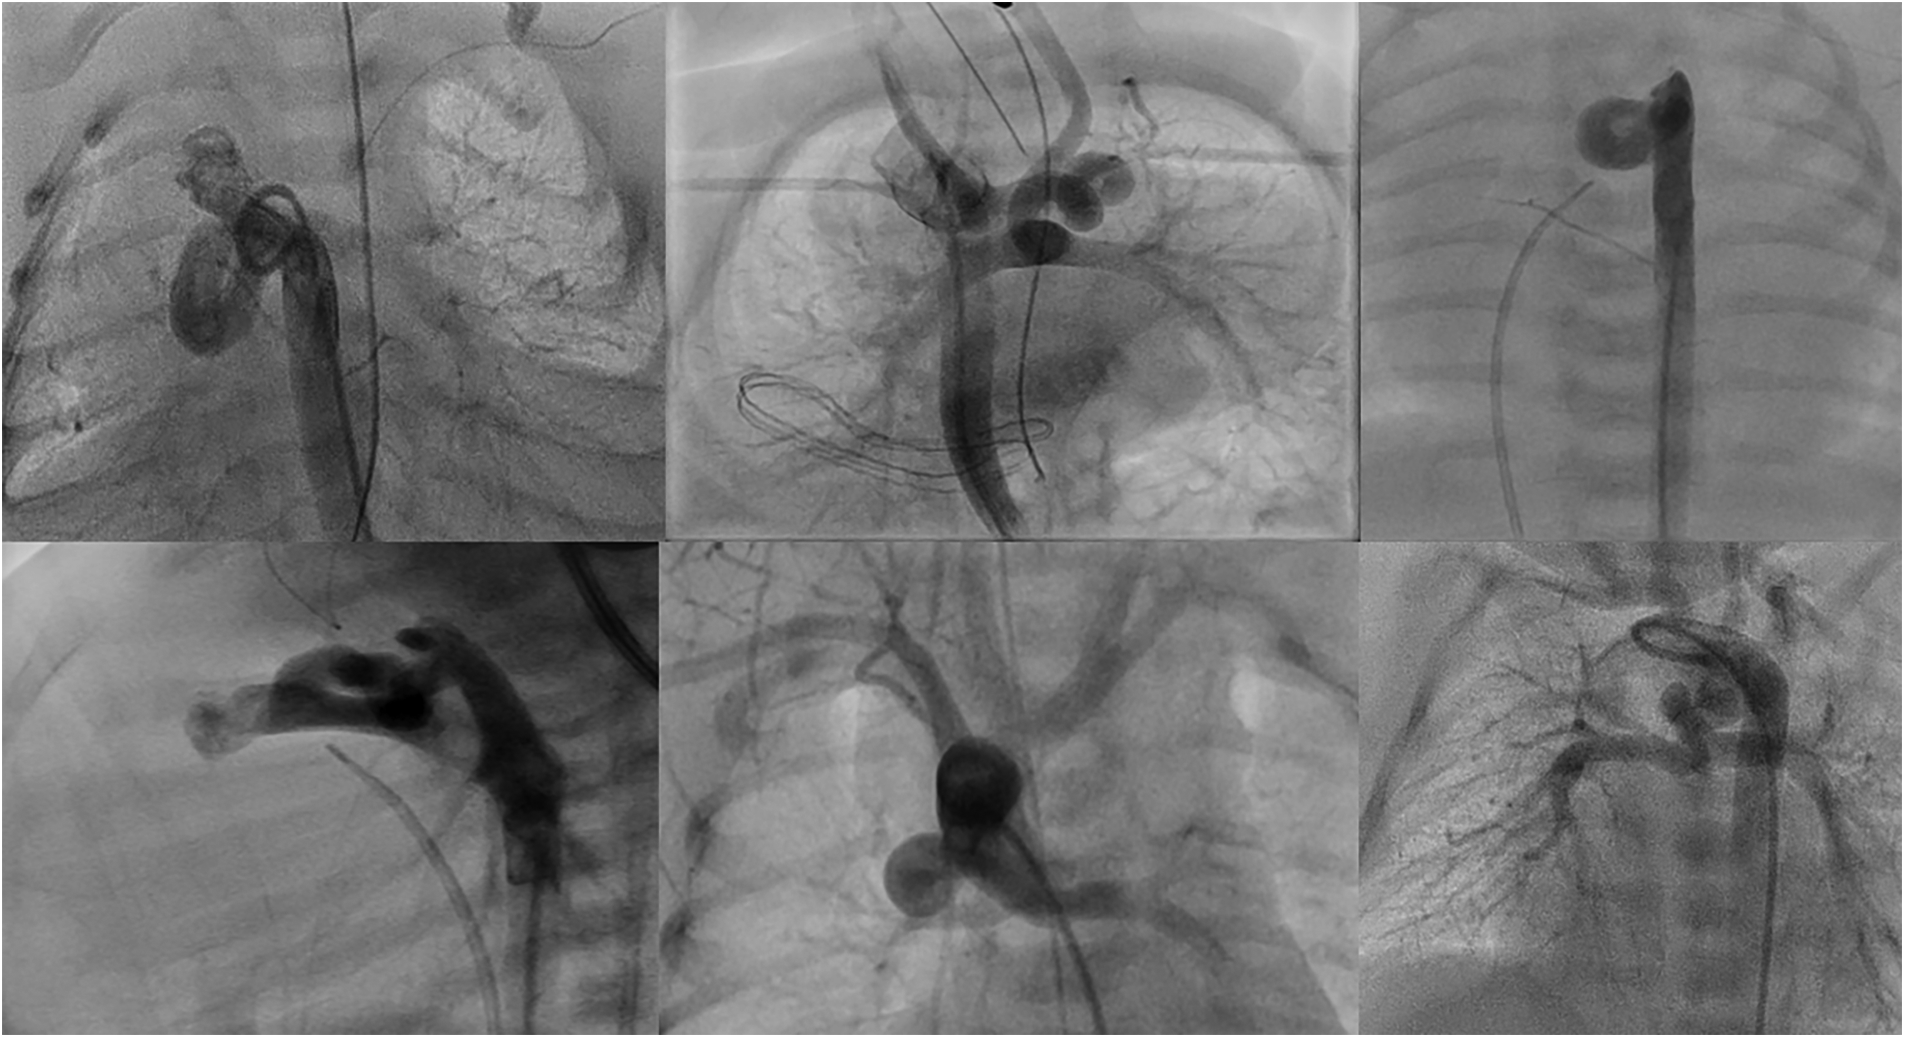

Figure 1

Types of ducts in congenital heart disease with duct-dependent pulmonary circulation. (A,B) Typical ducts originate from DAO in PA-IVS. (C) Tortuous duct originates from DAO with multiple complex curves. (D,E) Ducts originate from aortic arch with cervical course. (F) Duct originates from left subclavian artery. (G) Tortuous duct originates from DAO proximal to aortic arch. (H) Double ducts, the first originates from left subclavian artery and the second from the aortic arch. (I) Tortuous duct originates from aortic arch with multiple complex curves.